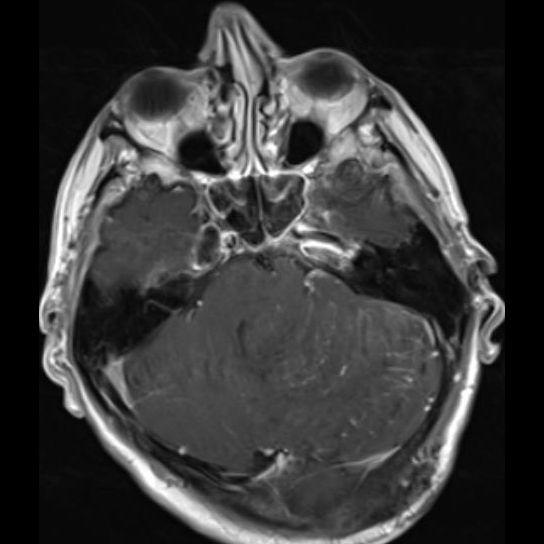

24 yaş, E

Baş ağrısı

Lhermitte-Duclos hastalığı (Dysplastic cerebellar gangliocytoma)